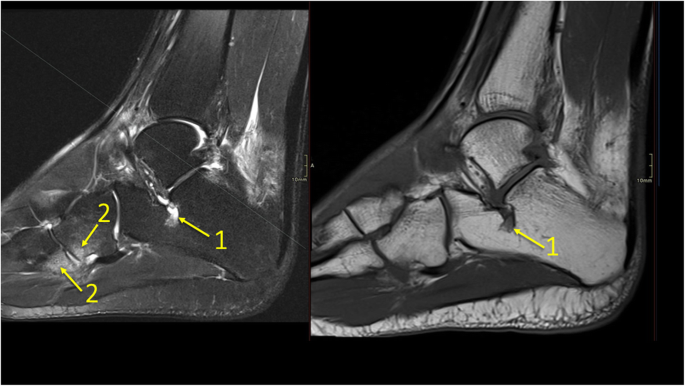

Bone marrow edema is not specific for osteonecrosis and may be seen in many musculoskeletal disorders, including osteomyelitis, osteoarthritis. Could the edema have spread? answered by dr. Bone marrow edema relate with rheumatoid arthritis, osteoarthritis, synovial tuberculosis, septic arthritis and traumatic arthritis.

The bone marrow edema (bme) is a common finding when evaluating patients with knee pain by magnetic resonance imaging (mri).

Bone marrow edema is frequently encountered on mri after an injury to the musculoskeletal system (sanders et although avulsive type bone marrow edema is less extensive than the impaction type, the. It can cause bleeding in the bone marrow, leading to severe pain. How we manage bone marrow edema—an interdisciplinary approach. american family physician: (2003) bone marrow edema and its relation to progression of knee osteoarthritis.